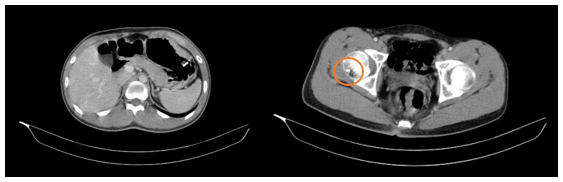

Hình 1

. Hình ảnh dày thành dạ dày đoạn thân vị. Ổ tiêu xương có viền đặc xương chỏm xương đùi phải (vòng tròn màu cam)